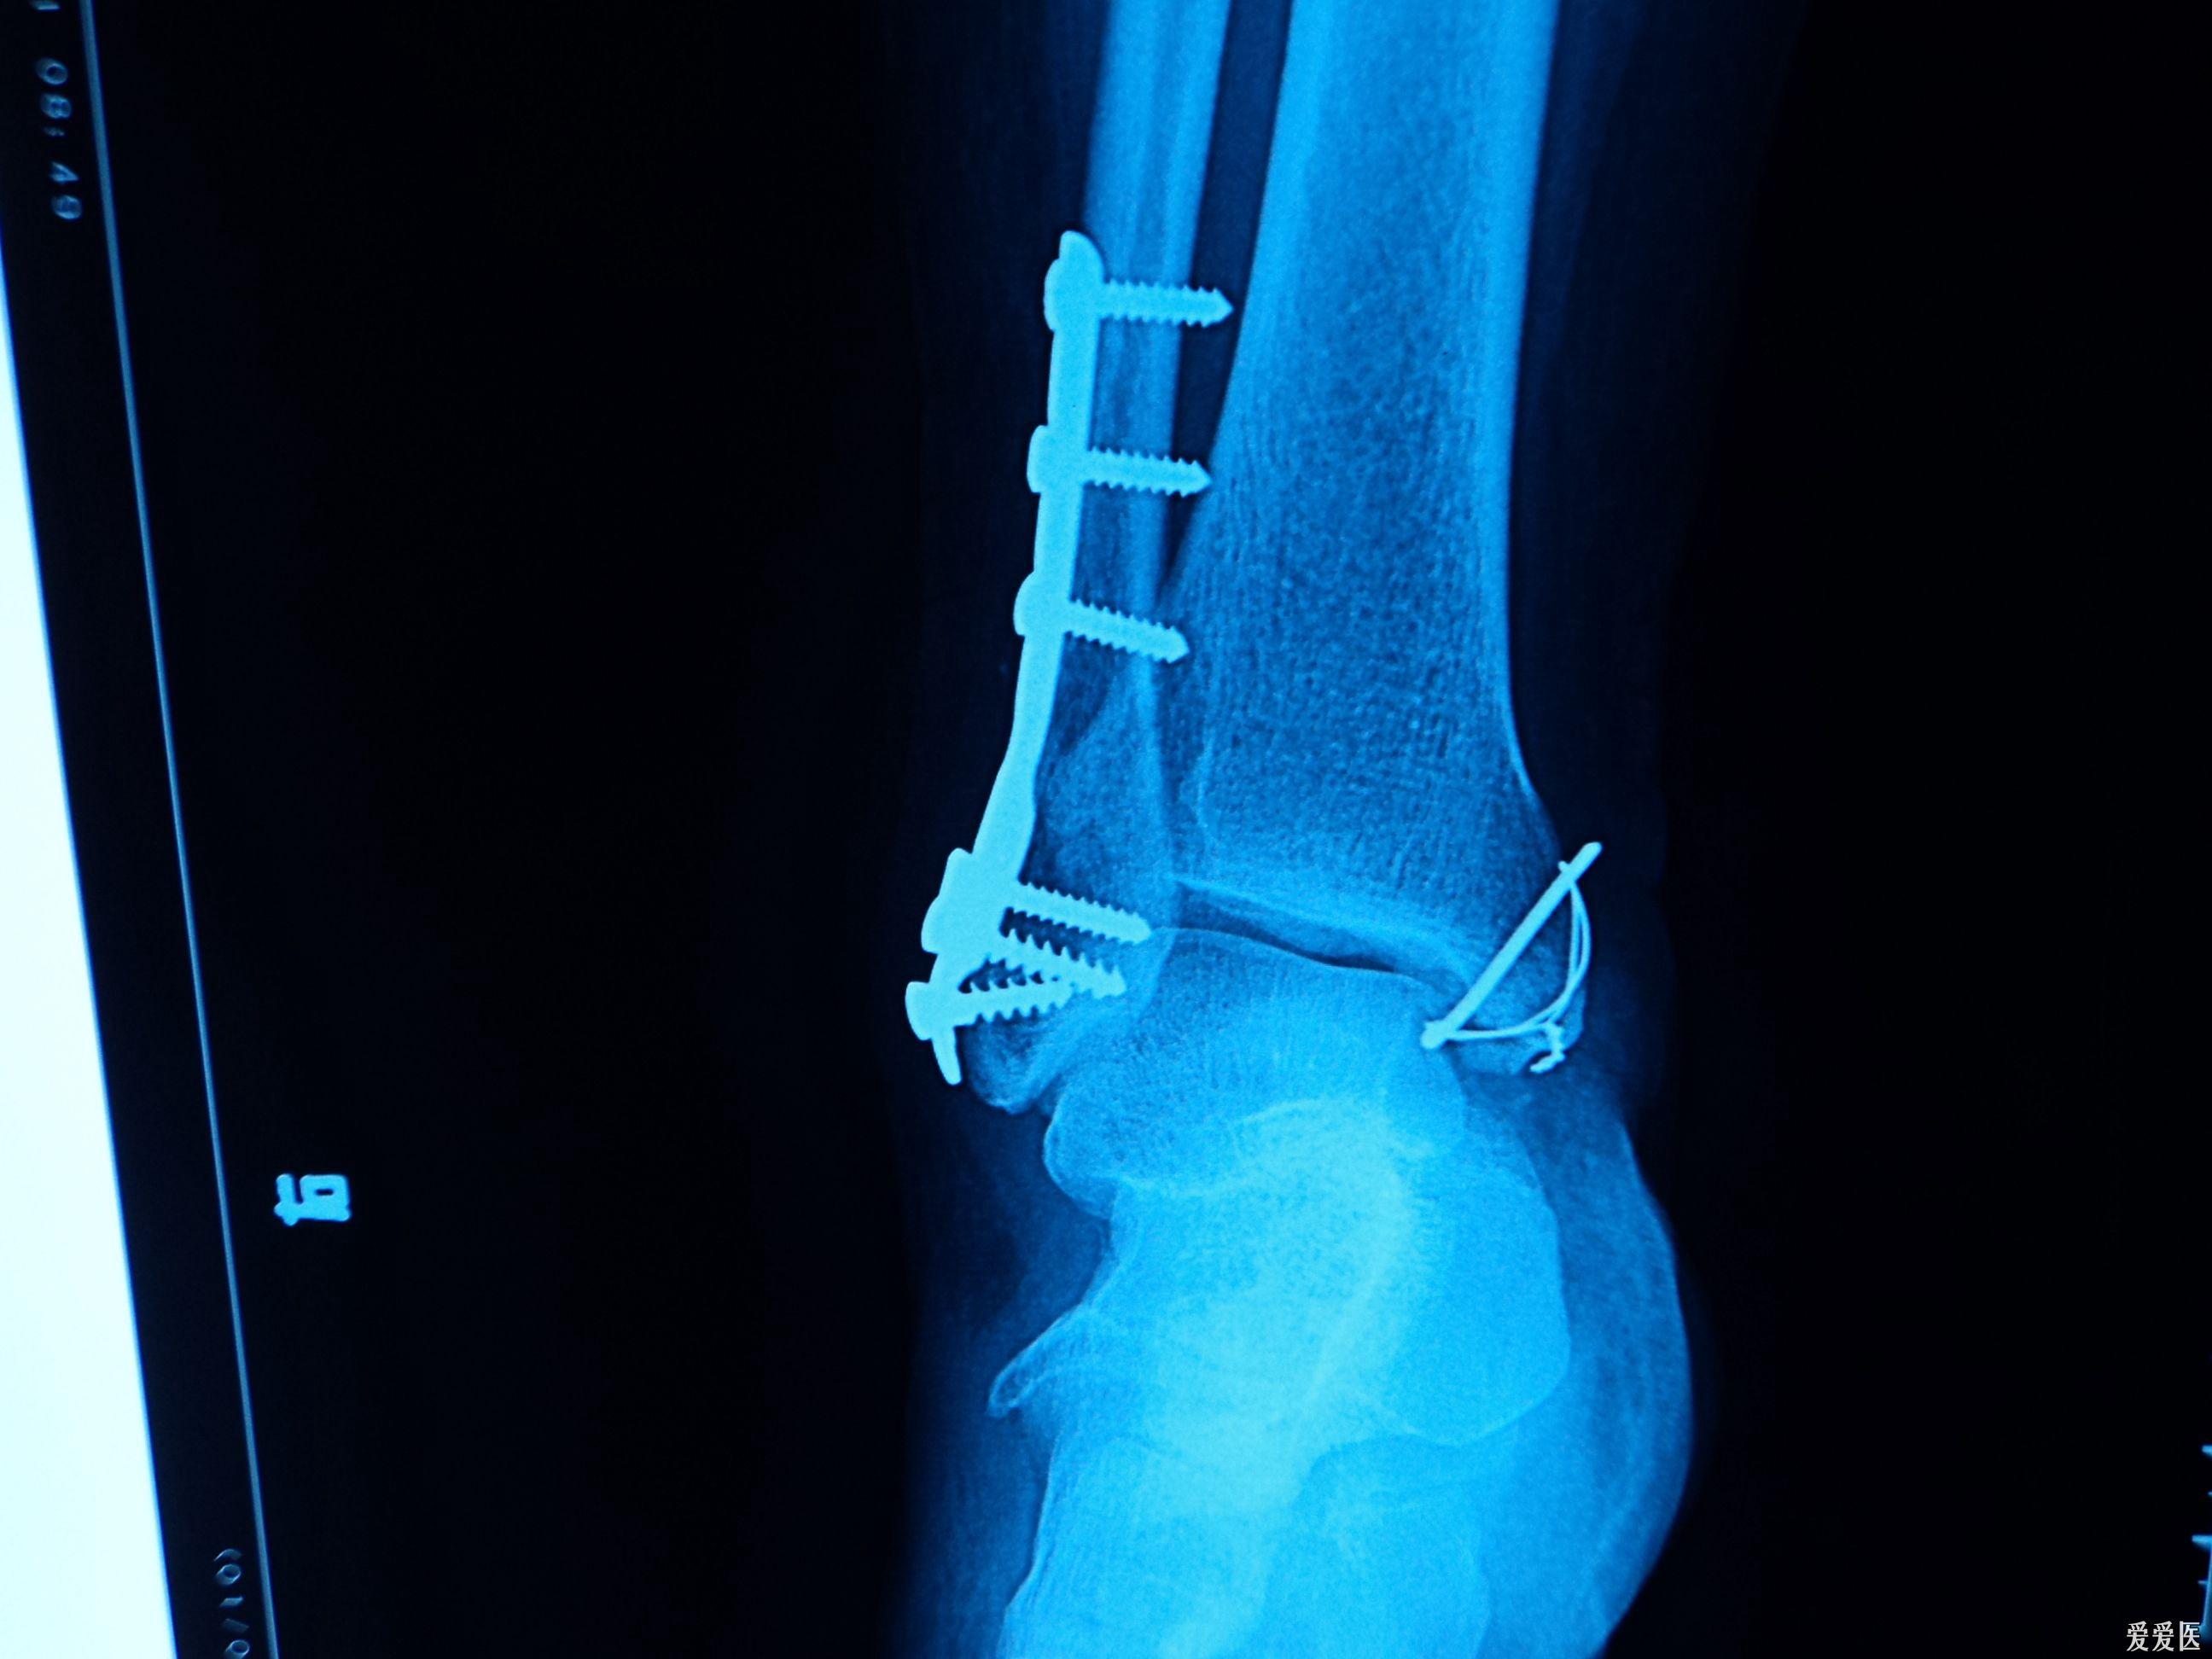

内外踝骨折术后

内外踝骨折切开复位内固定术